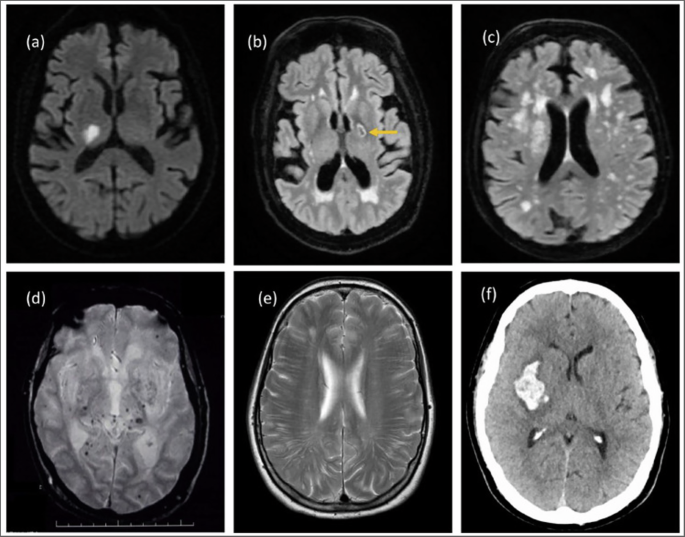

There are a panoply of underlying radiological and pathological vascular brain changes associated with VCID. To understand the current and future treatment targets of VCID, these lesions are briefly reviewed below (Figs. 1 and 2). In the 1970s and 80 s, the diagnosis of VaD was generally restricted to those who had experienced a stroke, referred to as post-stroke dementia. In addition to post-stroke dementia not being exclusively vascular in origin, we now recognize that VCID may be caused by various diseases of the large and small cerebral vessels, leading to thromboembolic disease, cerebral ischemia or hemorrhage, acute or chronic cerebral hypoperfusion, impaired angiogenesis and diminished oxygen and nutrient blood-brain barrier transport (see Table 2 for list of underlying pathologies) [17]. The developing understanding of these diverse pathophysiological mechanisms has allowed for a greater number of novel treatment approaches, that we will explore in later sections.

Schematic diagram summarizing the macroscopic lesions associated with VCID.

a Acute lacunar infarct in right thalamus on DWI. b Old cavitated lacune in posterior limb of left internal capsule on FLAIR. c Confluent white matter hyperintensities on FLAIR. d Deep CMB on gradient echo scan. e Enlarged PVS intracerebral. f Basal ganglia hemorrhage on CT. Image and description taken directly from “Markus Hugh S, de Leeuw Frank Erik. Cerebral small vessel disease: Recent advances and future directions. Int J Stroke. 2022;18:4–14 - Fig. 1” [167] under Creative Commons Attribution 4.0 License (https://creativecommons.org/licenses/by/4.0/) which permits any use, reproduction and distribution of the work without further permission.